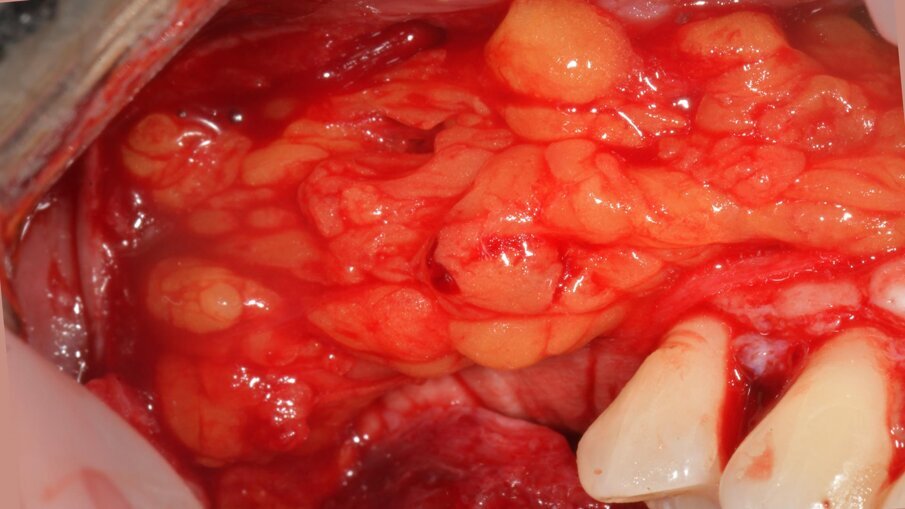

Successivamente, la griglia in titanio customizzata CAD/CAM (Yxoss CBR, Reoss, Geistlich) è stata prelevata dalla doppia busta sterile ed è stata riempita con il materiale da innesto (Fig. 16). La griglia è stata quindi posizionata in sito e fissata con quattro viti di osteosintesi, al fine di ottenere una stabilità assoluta (Fig. 17). È stata poi ricoperta da una membrana riassorbibile in collagene nativo (Biogide, Geistlich) stabilizzata a sua volta con chiodini in titanio (McBio, Geist-lich) (Fig. 18). Prima della chiusura del lembo primario, è stato isolato, prelevato, e avanzato il tessuto grasso della bolla di Bichat, per ridurre il rischio di esposizione e infezione della griglia sottostante17, essendo un tessuto estremamente ricco di cellule pluripotenti, in grado di differenziarsi per la guarigione di prima intenzione dell’area trattata (Fig. 19). Infine, i lembi chirurgici buccale e vestibolare sono stati suturati mediante una doppia linea di sutura, la prima costituita da punti a materassaio orizzontale, la seconda da punti singoli o doppi (Resorba Glycolon, Osteogenics) (Fig. 20). I lembi chirurgici sono stati accuratamente adattati per una chiusura per prima intenzione, senza tensioni, utilizzando una combinazione di suture a materassaio orizzontali e suture interrotte (Resorba Glycolon, Osteogenics) (Figg. 20, 21). Dopo l’intervento chirurgico, la paziente ha seguito un protocollo postoperatorio che includeva una terapia antibiotica (1 g di amoxicillina con acido clavulanico e 250 mg di metronidazolo ogni 8 ore per 7 giorni), e la disinfezione del cavo orale mediante risciacqui con clorexidina 0,2% per 2 minuti, tre volte al giorno, per 14 giorni.